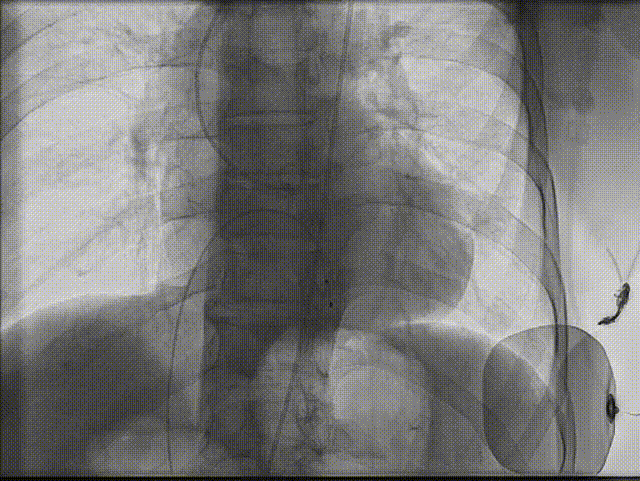

1.根据术前测量分析,采取右侧股动脉作为主入路,左股为辅入路,冠脉造影显示双侧冠脉灌注良好。

左冠造影

右冠造影

2.置入猪尾进行根部造影,造影可见主动脉根部大量钙化,瓣叶活动度低,冠脉灌注良好,中量反流。

根部造影